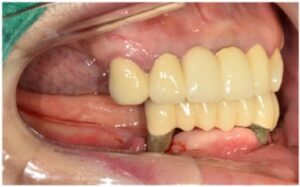

먼저 위턱 어금니와

아래턱 오른쪽 어금니의

지대주 제작을 위한

coping 인상채득을 진행하였는데요.

Fixture와 보철물을 연결해 주는 지대주를

개인의 구강 상황에 맞는

맞춤형 지대주를 이용하였으며

기공소에서 만들어온 임시 치아를 통해

최종 보철물을 제작하기 전

무너진 교합과 수직 고경을 회복시키고,

구강 근육 및 점막 안정화를 위한

시간을 가지기로 하였습니다.